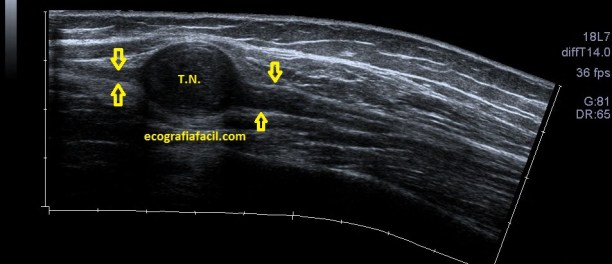

Mira la foto realizada con Panorama y estúdiala bien antes de seguir leyendo…

Los Tumores Neurogénicos (T.N.) son tumores de los Nervios, donde puede aparecer una lesión hipoecogénica y heterogéneaque antes y después de la lesión tienen un afilamiento (flechas amarillas) que se corresponde con la parte del Nervio no afectada y se continúa con el Nervio ecográficamente normal. Este hallazgo ecográfico es vital y además es diágnostico para el Radiólogo, en la mayoría de las ocasiones.